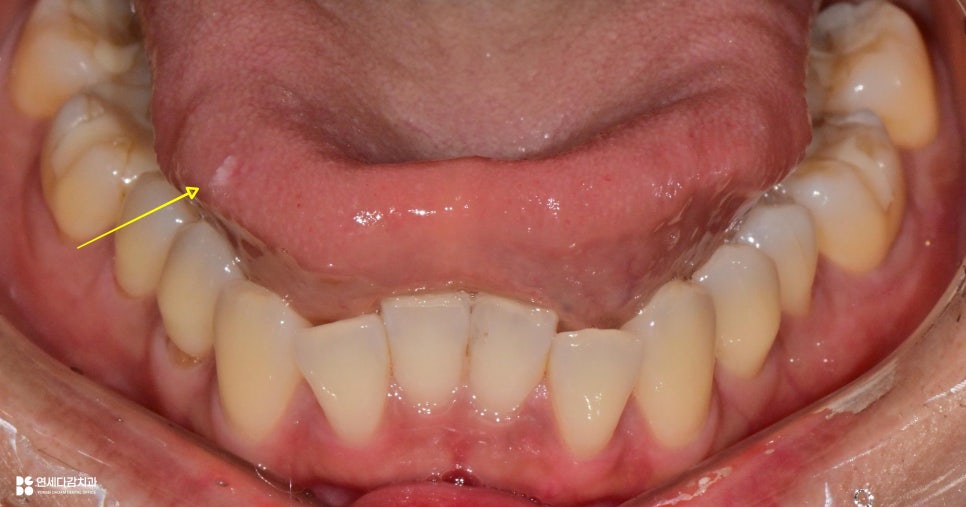

구강 유두종은 점막에 발생하는

돌출된 병변입니다.

표면이 하앟거나 분홍빛을 띠며

작은 돌기들이 모여 있는 형태가 많죠.

이 크기는 몇 밀리미터부터

1센티미터 이상까지 차이가 있습니다.

발생하는 부위도 다양하며,

혀, 연구개, 볼 점막, 입술 안쪽 등

어느 부위에나 나타납니다.

특히 혀에 생긴 경우에는

대화, 식사 시에도 자극을 받기 쉬워

불편감을 느끼는 분들이 많습니다.